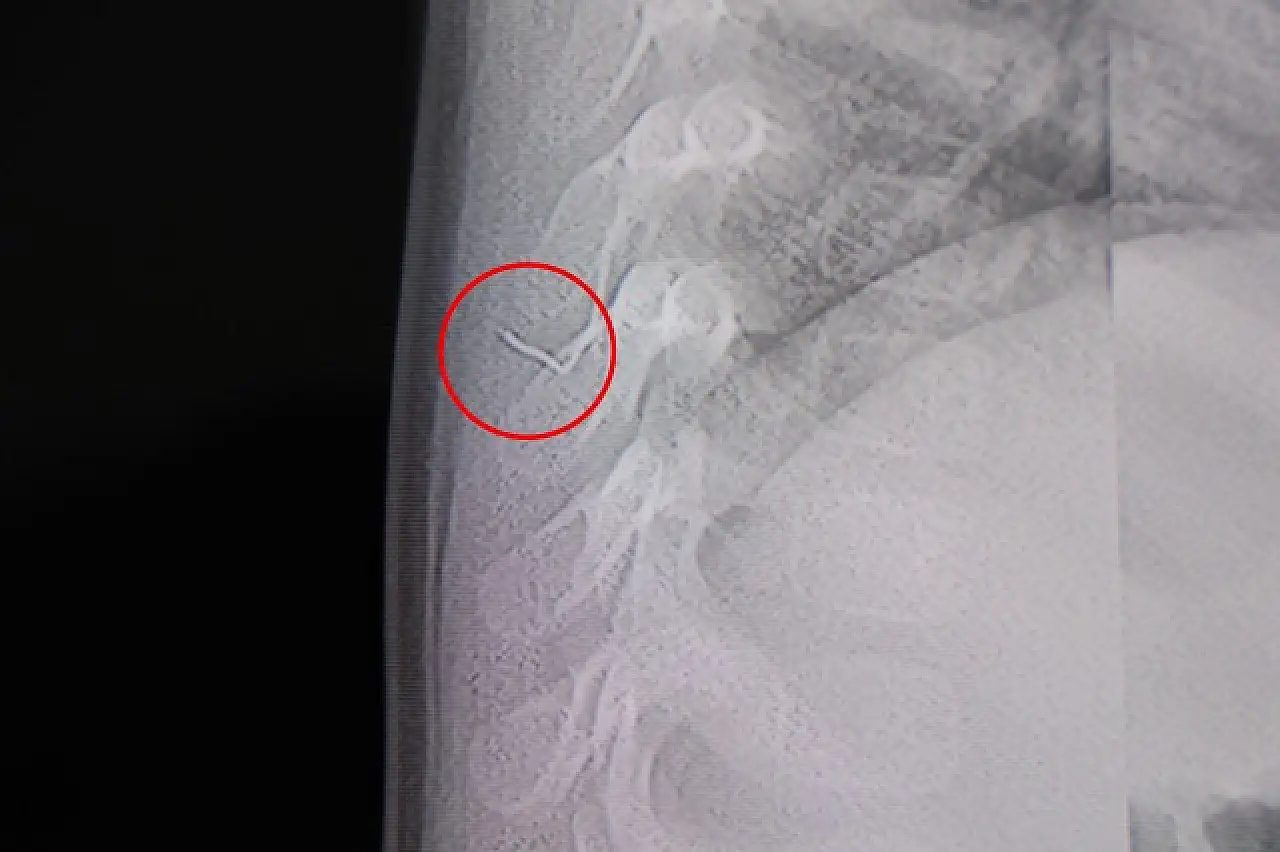

Kahramanmaraş'ta sırtüstü yatırıldığında sürekli ağlayan ve huzursuzlanan 1 yaşındaki bebeğin sırtından, akciğer zarına doğru ilerleyen yaklaşık 2 santimetrelik metal bir tel çıkarıldı. Uzmanlar, yabancı cismin alınmaması halinde ciddi enfeksiyonlara ve hayati risklere yol açabileceği uyarısında bulundu.

Hasta, genel anestezi uygulanmadan, lokal anestezi ve sedasyon eşliğinde gerçekleştirilen operasyonla tedavi edildi. Yapılan müdahalede, yabancı cismin tamamen çıkarıldığı belirtildi. Doktorlar, çıkarılan cismin ince bir zımba teline benzer metal tel olduğunu ve yaklaşık 2 santimetre uzunluğunda bulunduğunu açıkladı. Operasyonun ardından bebeğin sağlık durumunun iyi olduğu, gerekli kontrollerin yapılmasının ardından aynı gün taburcu edildiği öğrenildi.

“Sırtında yabancı bir cisim olduğu söylenmiş ancak çıkarılamayacağı ve 8 yaşına kadar beklenmesi gerektiği ifade edilmişti. Bize başvurduğunda yaptığımız tetkiklerde, cismin cilt altında, omurilik kanalına çok yakın ve akciğer zarına doğru ilerlediğini gördük. Hastamızı tamamen uyutmadan, lokal anestezi ve sedasyon eşliğinde müdahale ederek yabancı cismi tamamen çıkardık. Çıkardığımız cismin ince zımba teline benzer, yaklaşık 2 santimetre uzunluğunda metal bir tel olduğunu tespit ettik.”